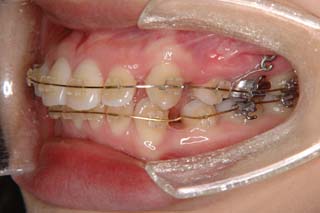

上顎前歯、下顎前歯の前突が見られます。大きな叢生は見られませんが、上下の口唇前突感も伴います。このような不正咬合を上下顎前突と言います。審美的な事もさることながら、歯軸の傾斜の問題から歯にかかるベクトルが良くない事、口唇の筋肉の緊張を強いるような不調和を示す事などから、不正咬合の一つとして考えられています。上顎前突傾向も伴っていますので、積極的に上顎前歯の後退を行う目的で、上顎に固定源となる 目的外使用の オーソアンカー SMAPシステム を装着しました。現在では、歯科矯正用アンカースクリュー(デュアルトップオートスクリュー、ISAアドバンスなど)といった、医療機器認証番号がある製品を用いることが多くなりました。

通常の矯正治療であれば、上顎の固定源として用いるのはヘッドギアという装置です。しかしながら、現状の日本では夜間使用以上の連続使用は難しいでしょう。ちなみにアメリカの学生は、授業中でもヘッドギアを装着してくれるみたいです。さぼり気味な人だと、ヘッドギアの効果が少なく、矯正治療が終わった後なのに、出っ歯の人もいるかも知れません。

歯を抜いた隙間を閉じる時、しっかり留めておかないと前歯が下がるだけでなく奥歯も前に寄ってきます。沢山、前歯を下げたい時には、奥歯と前歯を引っ張るのをやめて、前歯と別の固定源(歯科矯正用アンカースクリューなど)を引っ張ります。